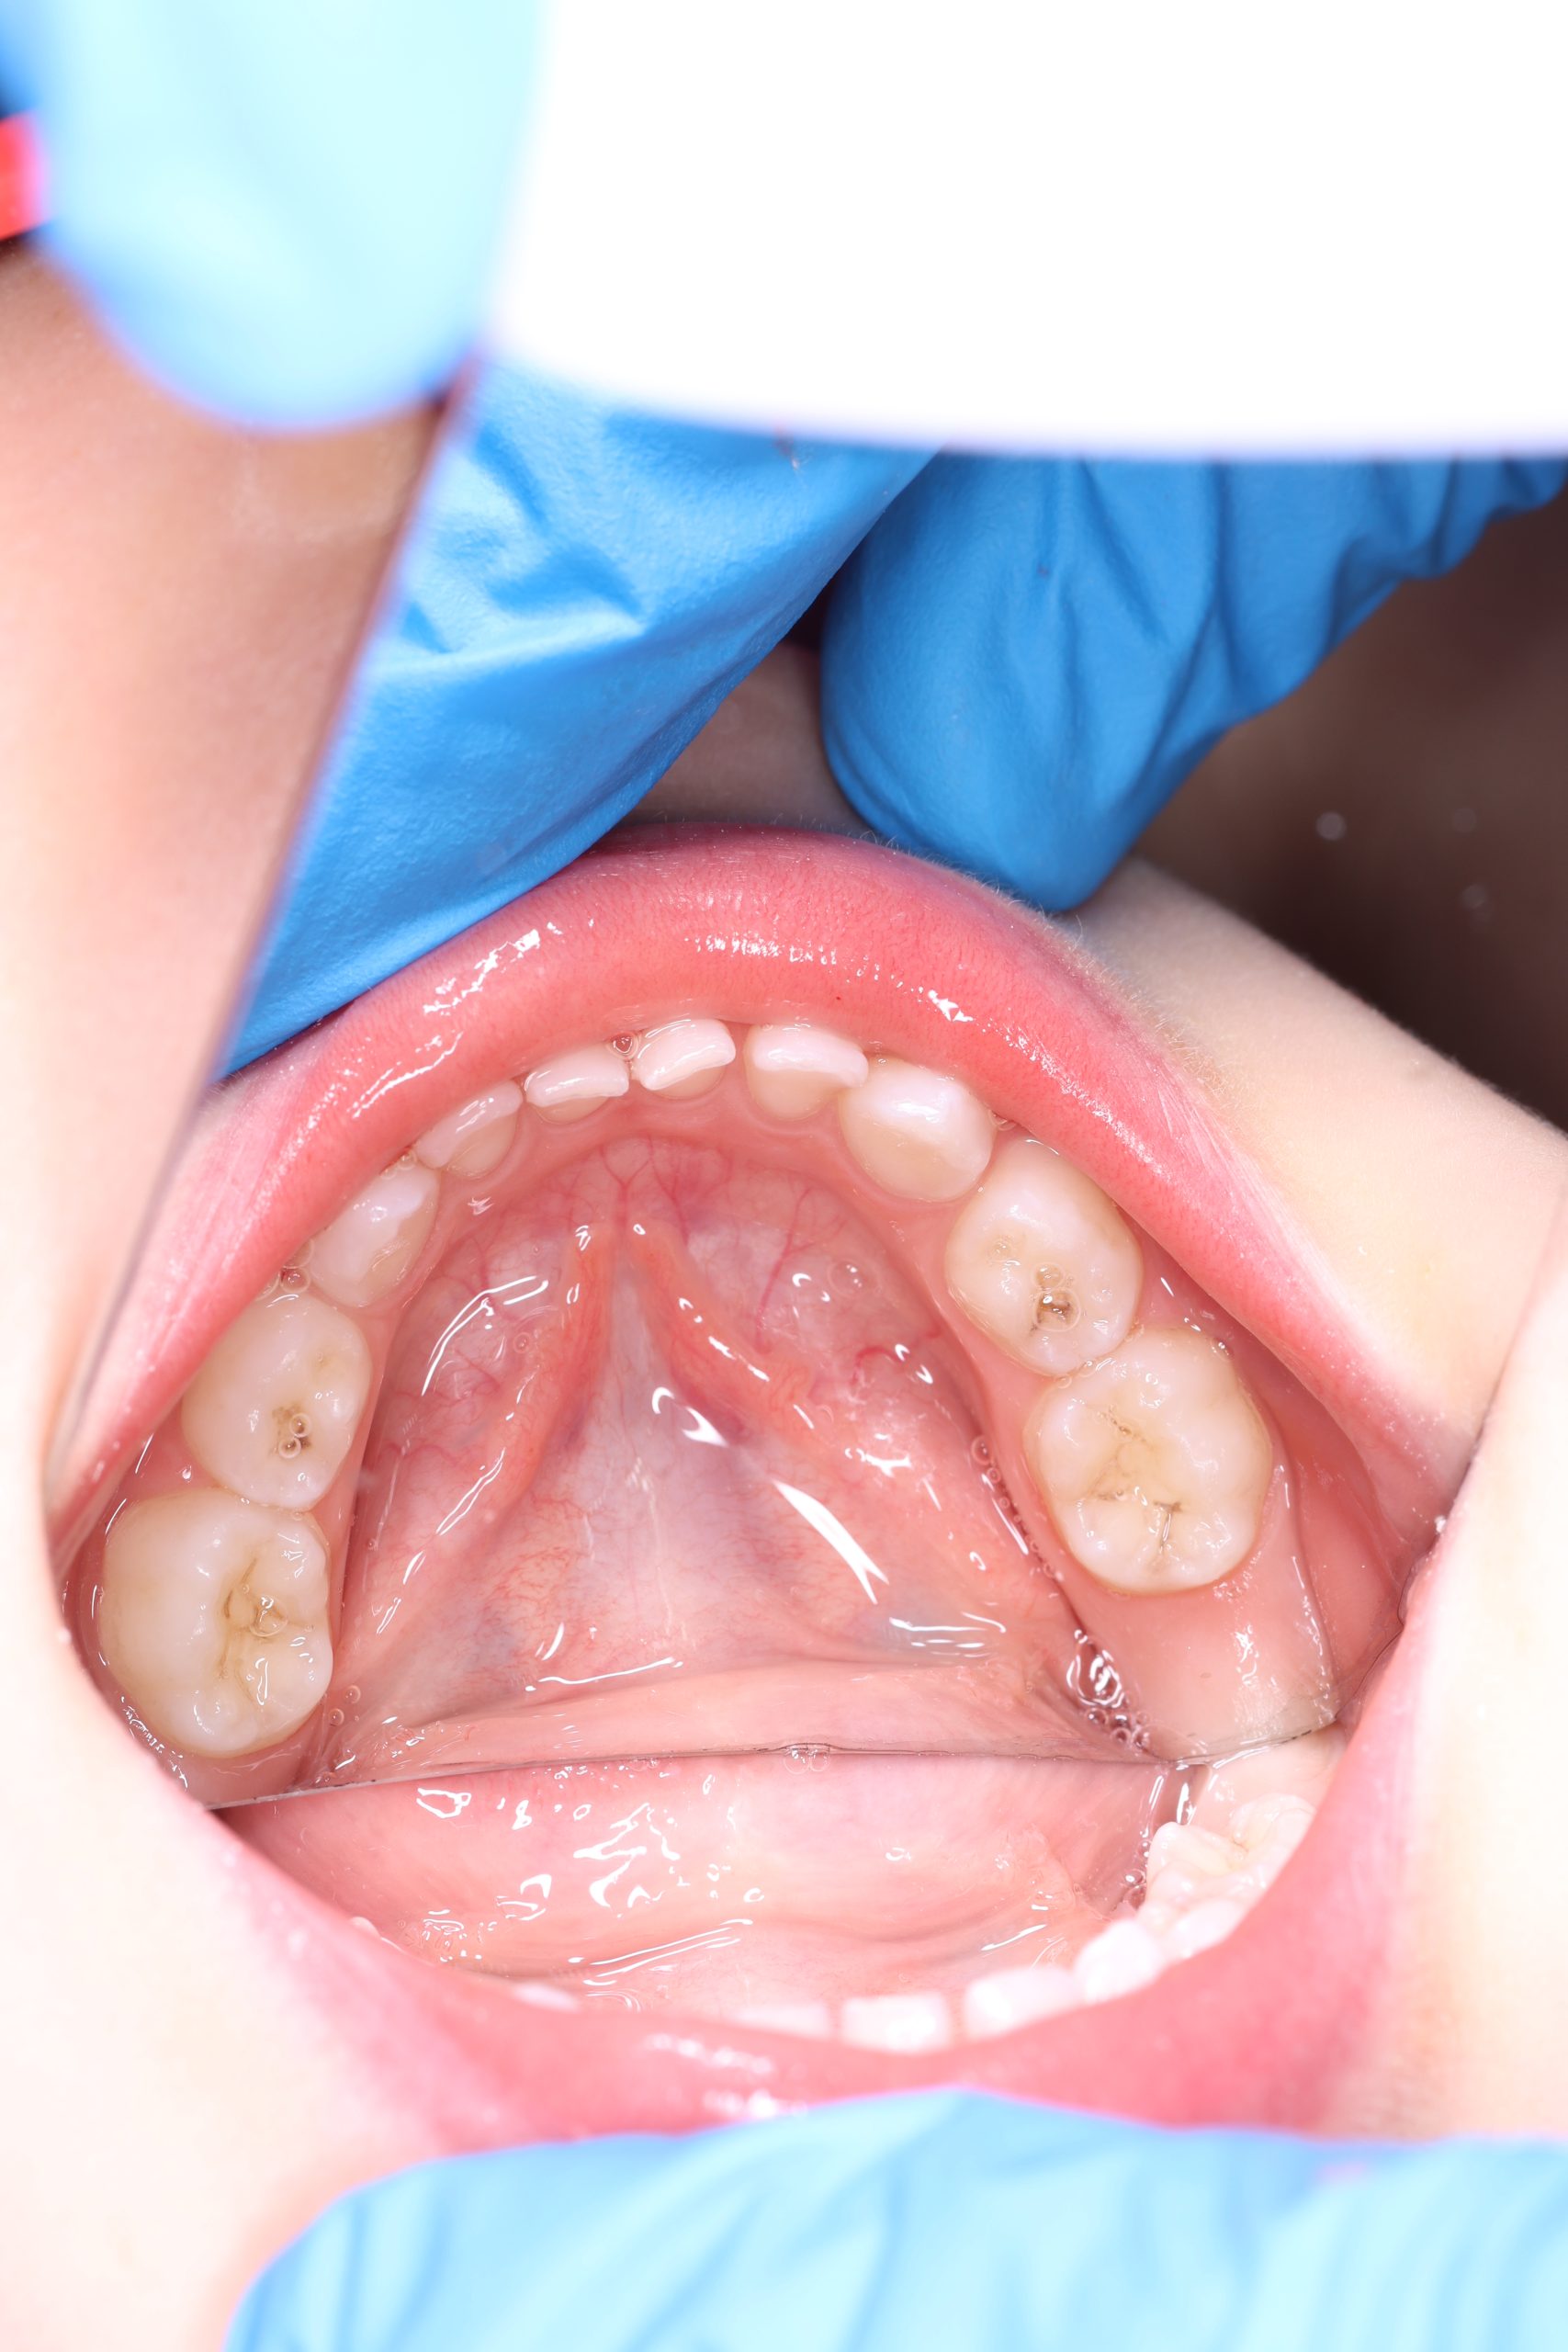

GBT (Guided Biofilm Therapy) is a modern, safe protocol for professional dental cleaning developed in Switzerland. For children, we use it to gently remove plaque, prevent cavities, and teach proper brushing — with plaque-disclosing dye and AirFlow technology starting from age 4–5.

- Detailed Examination

We examine the condition of teeth, gums, and bite. - Plaque Disclosure with Special Indicators